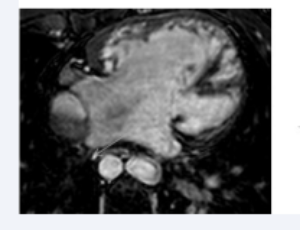

AbstractBackground: The main pathological manifestations of myocardial fibrosis are the proliferation of myocardial fibroblasts and the mass deposition of collagen fibers in myocardial tissue. It is a common feature of all cardiovascular diseases. Studies ha.....